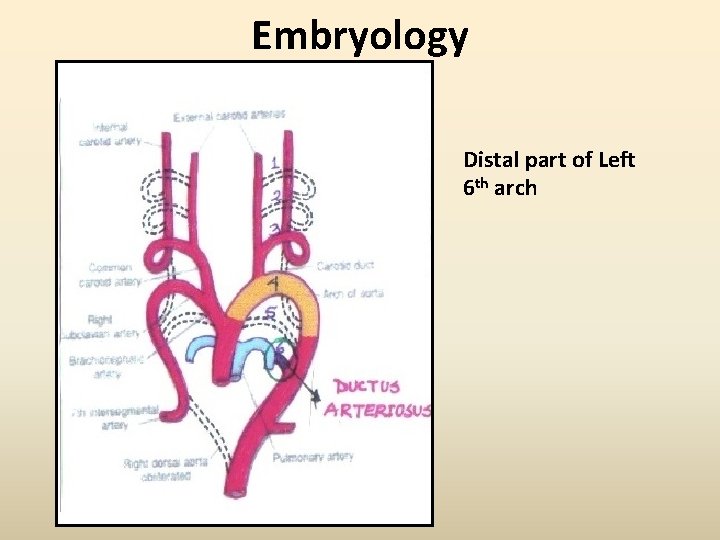

Embryology Distal part of Left 6 th arch